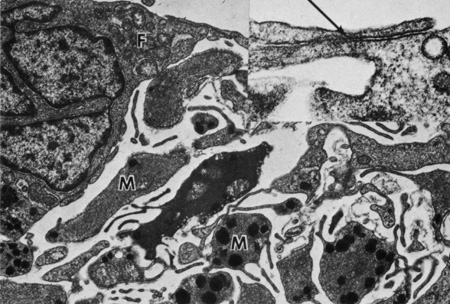

Fibroblasts are prominent on the iris surface. Transmission electron microscopic examination of these fibroblasts reveals abundant mitochondria, rough endoplasmic reticula, free ribosomes, and bundles of filaments (Fig. 9). Some fibroblasts have basal bodies in their cytoplasm, with associated cilia projecting into the anterior chamber (Figs. 10 and 11). Melanocytes are most often found just beneath fibroblasts and contain mitochondria, smooth and rough endoplasmic reticula, free ribosomes, and melanin granules in various stages of development (Fig. 12). The blood vessels and nerve fibers of the anterior border layer are similar to those in the deeper stroma and are discussed later.29

Fig. 9. The anterior border of the iris is composed of a discontinuous layer of fibroblasts (F) and interspersed collagen fibrils (arrows) (×13,800). Inset shows fibroblasts and a meshwork of collagen connecting fibroblasts (×40,500).

Fig. 12. Inset shows a junctional complex (arrow) forming the anterior border layer of the iris (scanning electron microscopy, ×1500). Melanocytes (M) are present beneath the fibroblasts (F) of the anterior border layer (×10,500).